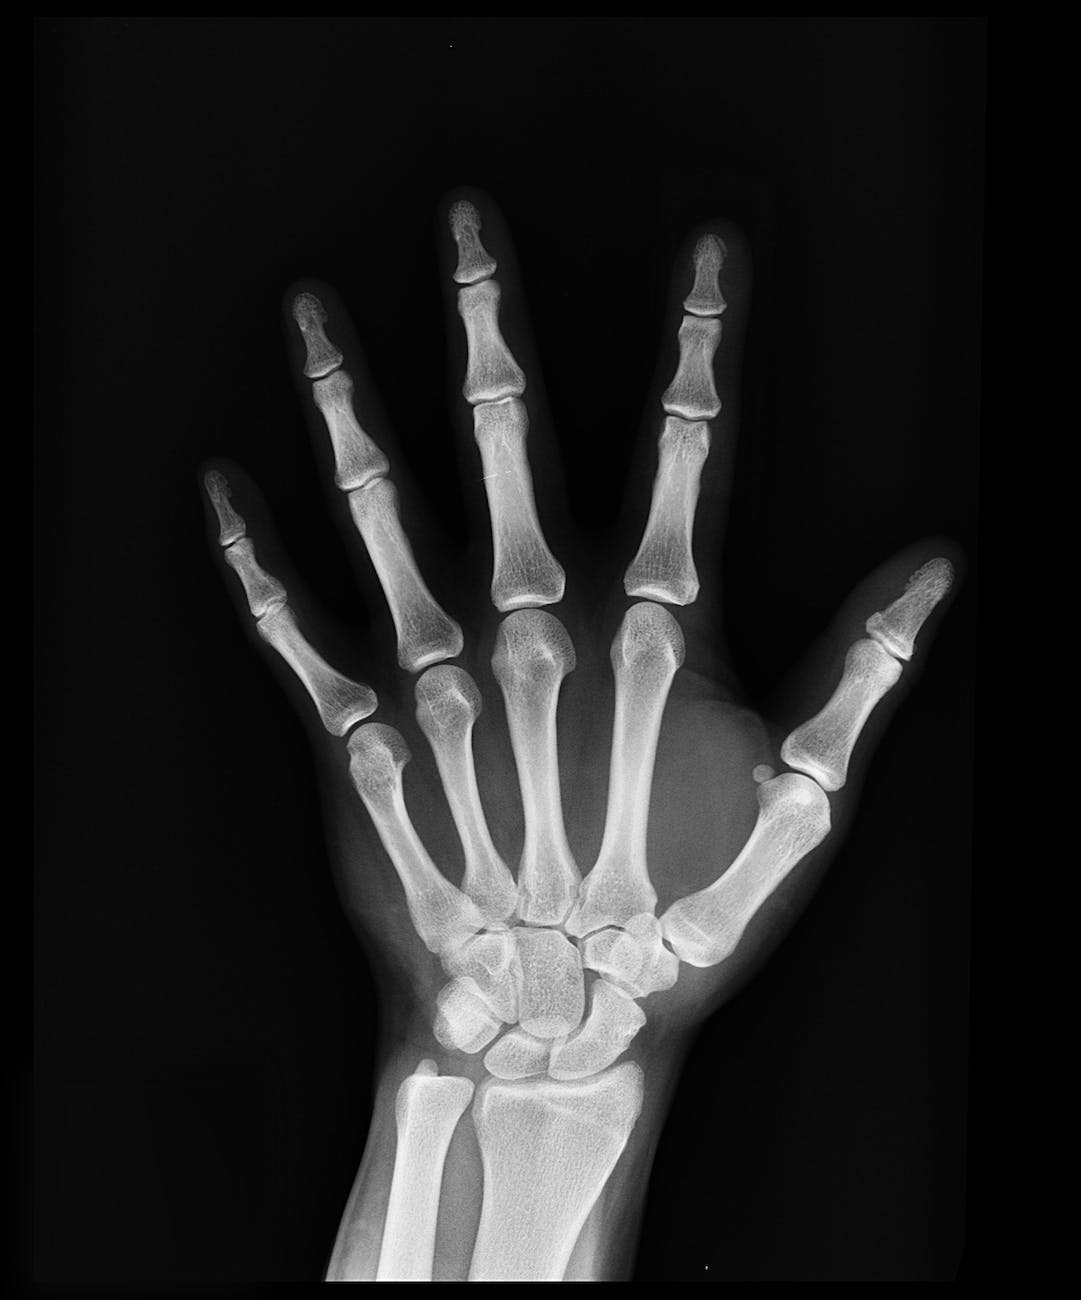

Традиционните тестове за остеопороза разглеждат костната минерална плътност. Чрез образен тест Вашият лекар ще може определи костната плътност на цялото ви тяло или в различни части на тялото ви, където може да сте по-уязвими към счупвания, като гръбначния стълб и бедрената кост.

Вашият лекар може също да назначи рентгенова снимка или други образни изследвания, преди да постави диагноза. Тези тестове могат да помогнат за откриване на автоимунни заболявания като анкилозиращ спондилит.